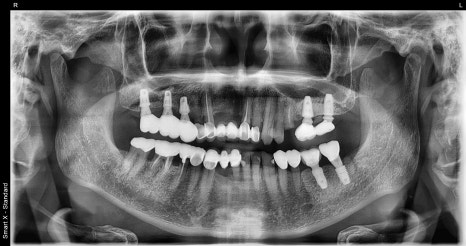

왼쪽 사진: 첫 내원당시 촬영한 파노라마 엑스레이 입니다. 기존임플란트는 보철은 깨져있었지만 뿌리는 튼튼한 상태입니다.

오른쪽 사진: #25(왼쪽 위 두번째 작은어금니)는 많이 썩어서 뿌리만 남은상태였습니다. 발치 후 바로 임플란트 식립을 권유드렸습니다.